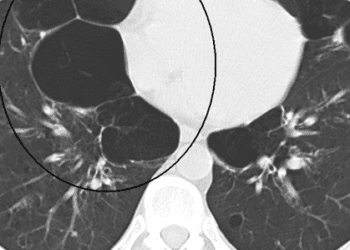

1. The presence of emphysema-like lung detected on computed tomography (CT) scans was associated with increased all-cause mortality in patients ...

Image: PD 1. Lung-volume-reduction surgery significantly improves exercise capacity, but not overall survival, in patients with emphysema when compared with ...